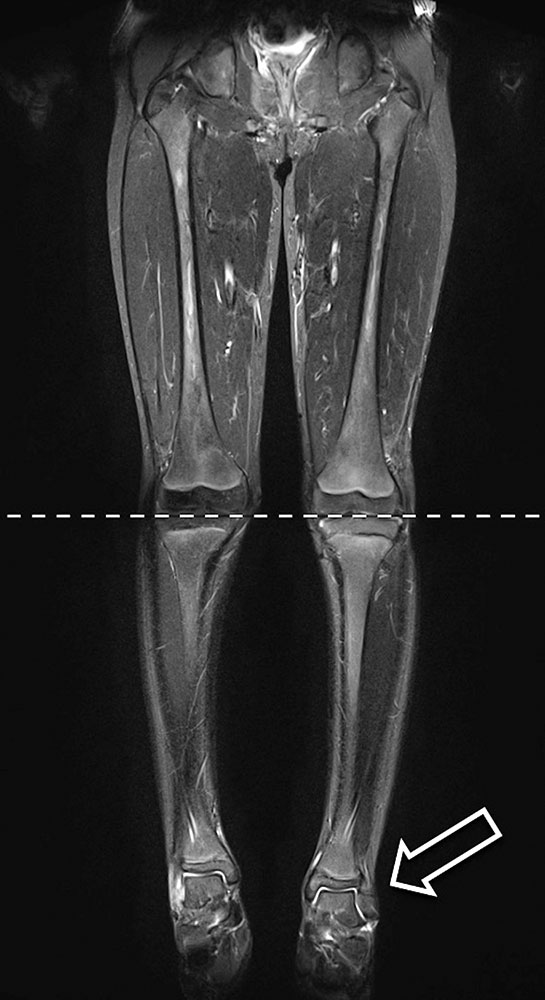

Die koronare fettgesättigte T2-Sequenz der MRT der beiden Beine zeigt eine Beinlängendifferenz zugunsten des linken Beines (Pfeil) bei AVM der linken unteren Extremität (nicht mit dargestellt). © Uller